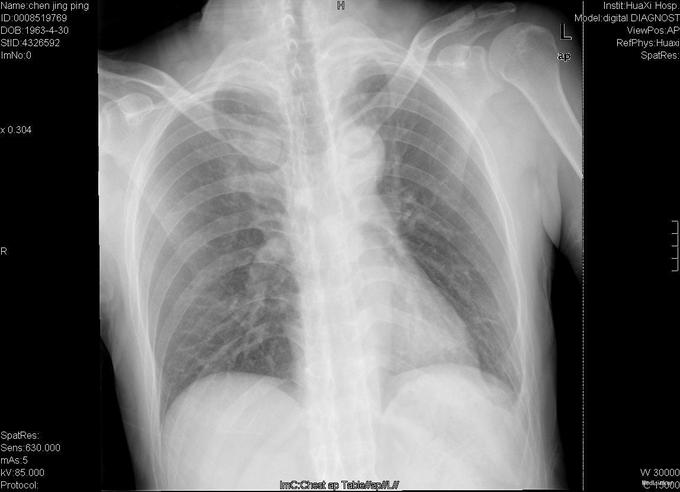

查体:跛行步态,强迫体位,脊柱强直后凸畸形,活动受限。右髋强直畸形,压痛、叩痛,无瘢痕、窦道,无皮损、皮癣,活动受限。双下肢感觉无明显异常。 辅助检查:x线片:脊柱呈"竹节样"改变,腰椎小关节间隙模糊,双侧骶髂关节及右髋关节间隙消失,骨性融合。